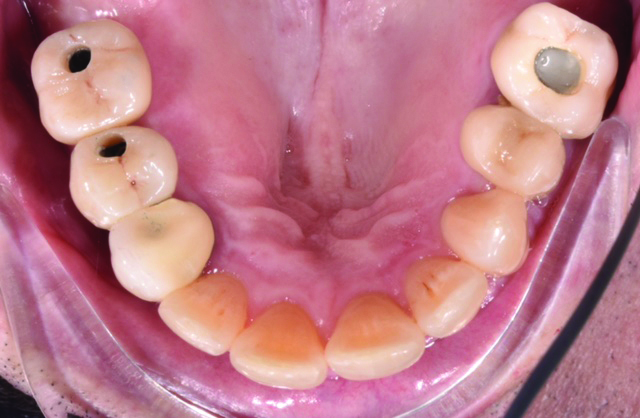

Following previous extractions of non-restorable teeth Nos. 3 and 4, a healthy, 66-year-old male presented for implant placement. NobelParallel Conical Connection RP implants (Nobel Biocare; nobelbiocare.com) were placed for No. 3 at 5 mm x 8.5 mm and No. 4 at 4.3 mm x 11.5 mm under local anesthesia. They were torqued down to >35 Ncm at the time of placement. Healing abutments were immediately placed. The patient tolerated the procedure well (Figure 1).

Fig 1. Occlusal view of maxillary arch with healing caps removed from implant fixtures in upper right quadrant.

Figure 1